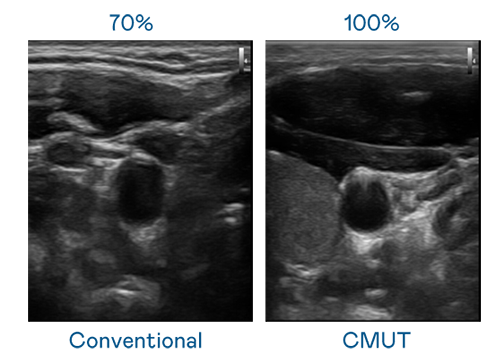

CMUT 技术是一种用电容式微机电元件来产生超音波讯号的技术。与传统 PZT 压电式技术相比,CMUT 频宽增加 30%,更宽频的超音波讯号让影像解析度大幅提升,是实现高影像品质医疗超音波扫描、促进精准医疗发展的关键技术。

超音波影像的解析度高低,首先取决于探头能发出的讯号频宽。yd12399云顶 CMUT 可提供高清晰的超音波讯号,提供高频宽、高灵敏度、影像纹理细节更高的超音波影像,协助医护人员缩短影像判读时间及利用精准的医疗影像进行诊断。